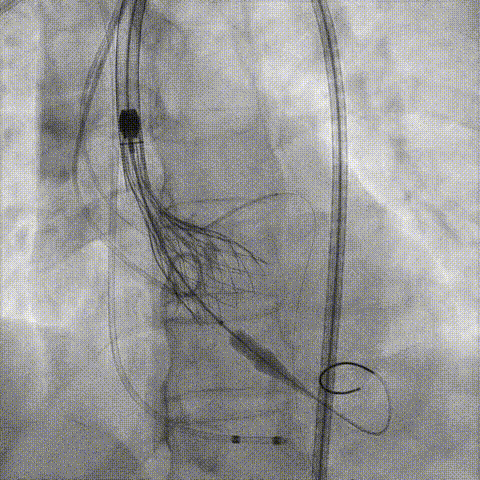

冠脉造影

手术策略和器械选择

预置Telescope™导引延长导管及导丝保护左冠,

18mm球囊预扩张再次评估冠脉闭塞风险。

介入经过及结果

Telescope™+Runthrough

18mm*40mm 预扩张

预埋 Resolute Integrity 3.5*26mm

再次评估左冠开口

第一次释放

再次评估左冠开口,考虑调整瓣膜深度

回收后调整深度,再次释放

评估左冠开口

左冠开口切线位造影

决定左冠烟囱支架保护冠脉

调整支架位置

释放冠脉支架

释放瓣膜

造影评估

支架内后扩张

根部造影